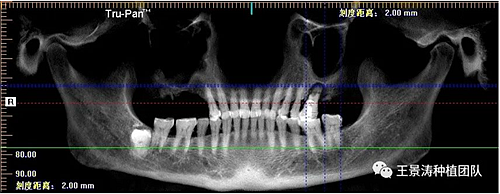

左側(cè)下頜第二磨牙及右側(cè)下頜第一磨牙同時(shí)即刻種植病例。患者年輕女性,無(wú)系統(tǒng)性疾病。37及46殘冠及殘根,且46劈裂,無(wú)法冠修復(fù),必須拔除。37根尖慢性炎癥,大量肉芽組織存在,46根分叉較高,根分叉骨質(zhì)尚可。CBCT示:根尖骨質(zhì)至下牙槽神經(jīng)管距離可滿足種植體的初期穩(wěn)定性,遂考慮即刻種植,并在種植體周邊填入骨粉并覆蓋骨膜,雙側(cè)的種植體初期穩(wěn)定性相差無(wú)幾,但考慮到37根尖慢性炎癥較大,遂給予埋入式種植。